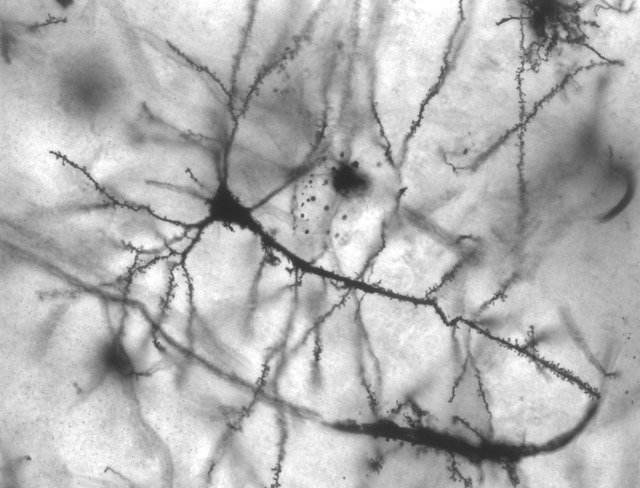

人生って結局脳からいかに効率よく快楽物質出すかゲーだよな Twitter Facebook はてブ LINE コピー 2022.08.29 スポンサーリンク 1: 風吹けば名無し 2022/08/29(月) 18:27:46.78 ID:b04FiK+Y0NIKU でも裏技使って薬に頼るとゲームがバグる模様 続きを読む